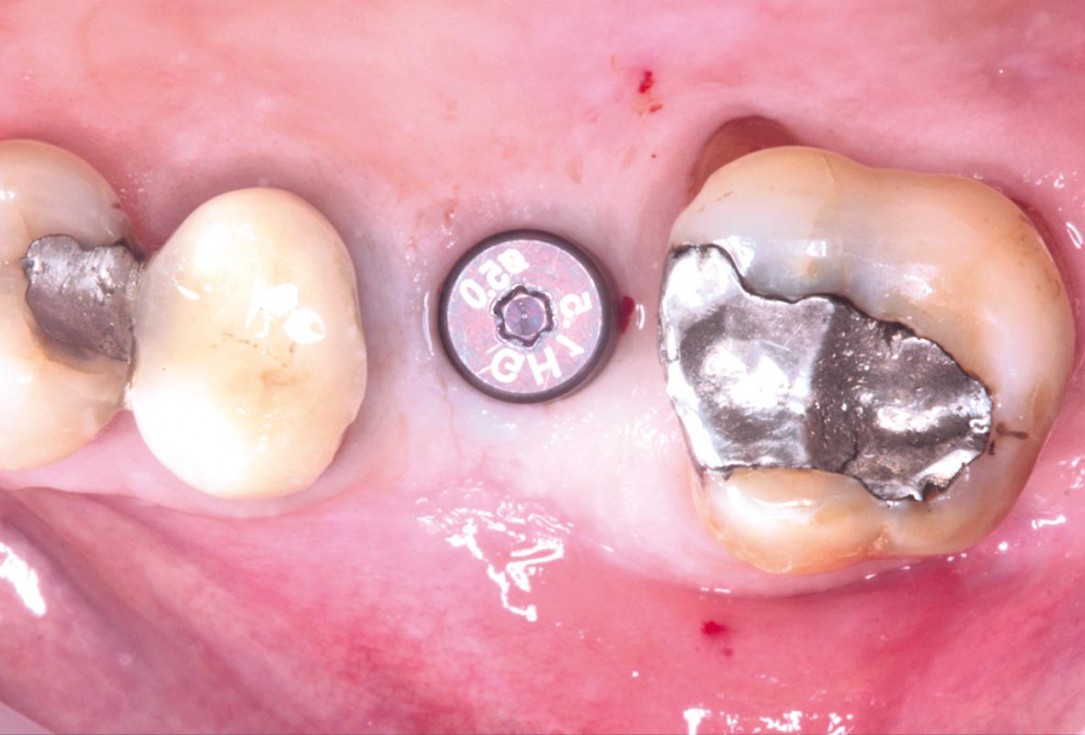

28/35 - Application of the healing cap after the second stageMaxillary sinus cyst removal using the Crocodile Technique and subsequent lateral sinus lift - Dres. C. Scognamiglio and A. Perucchi